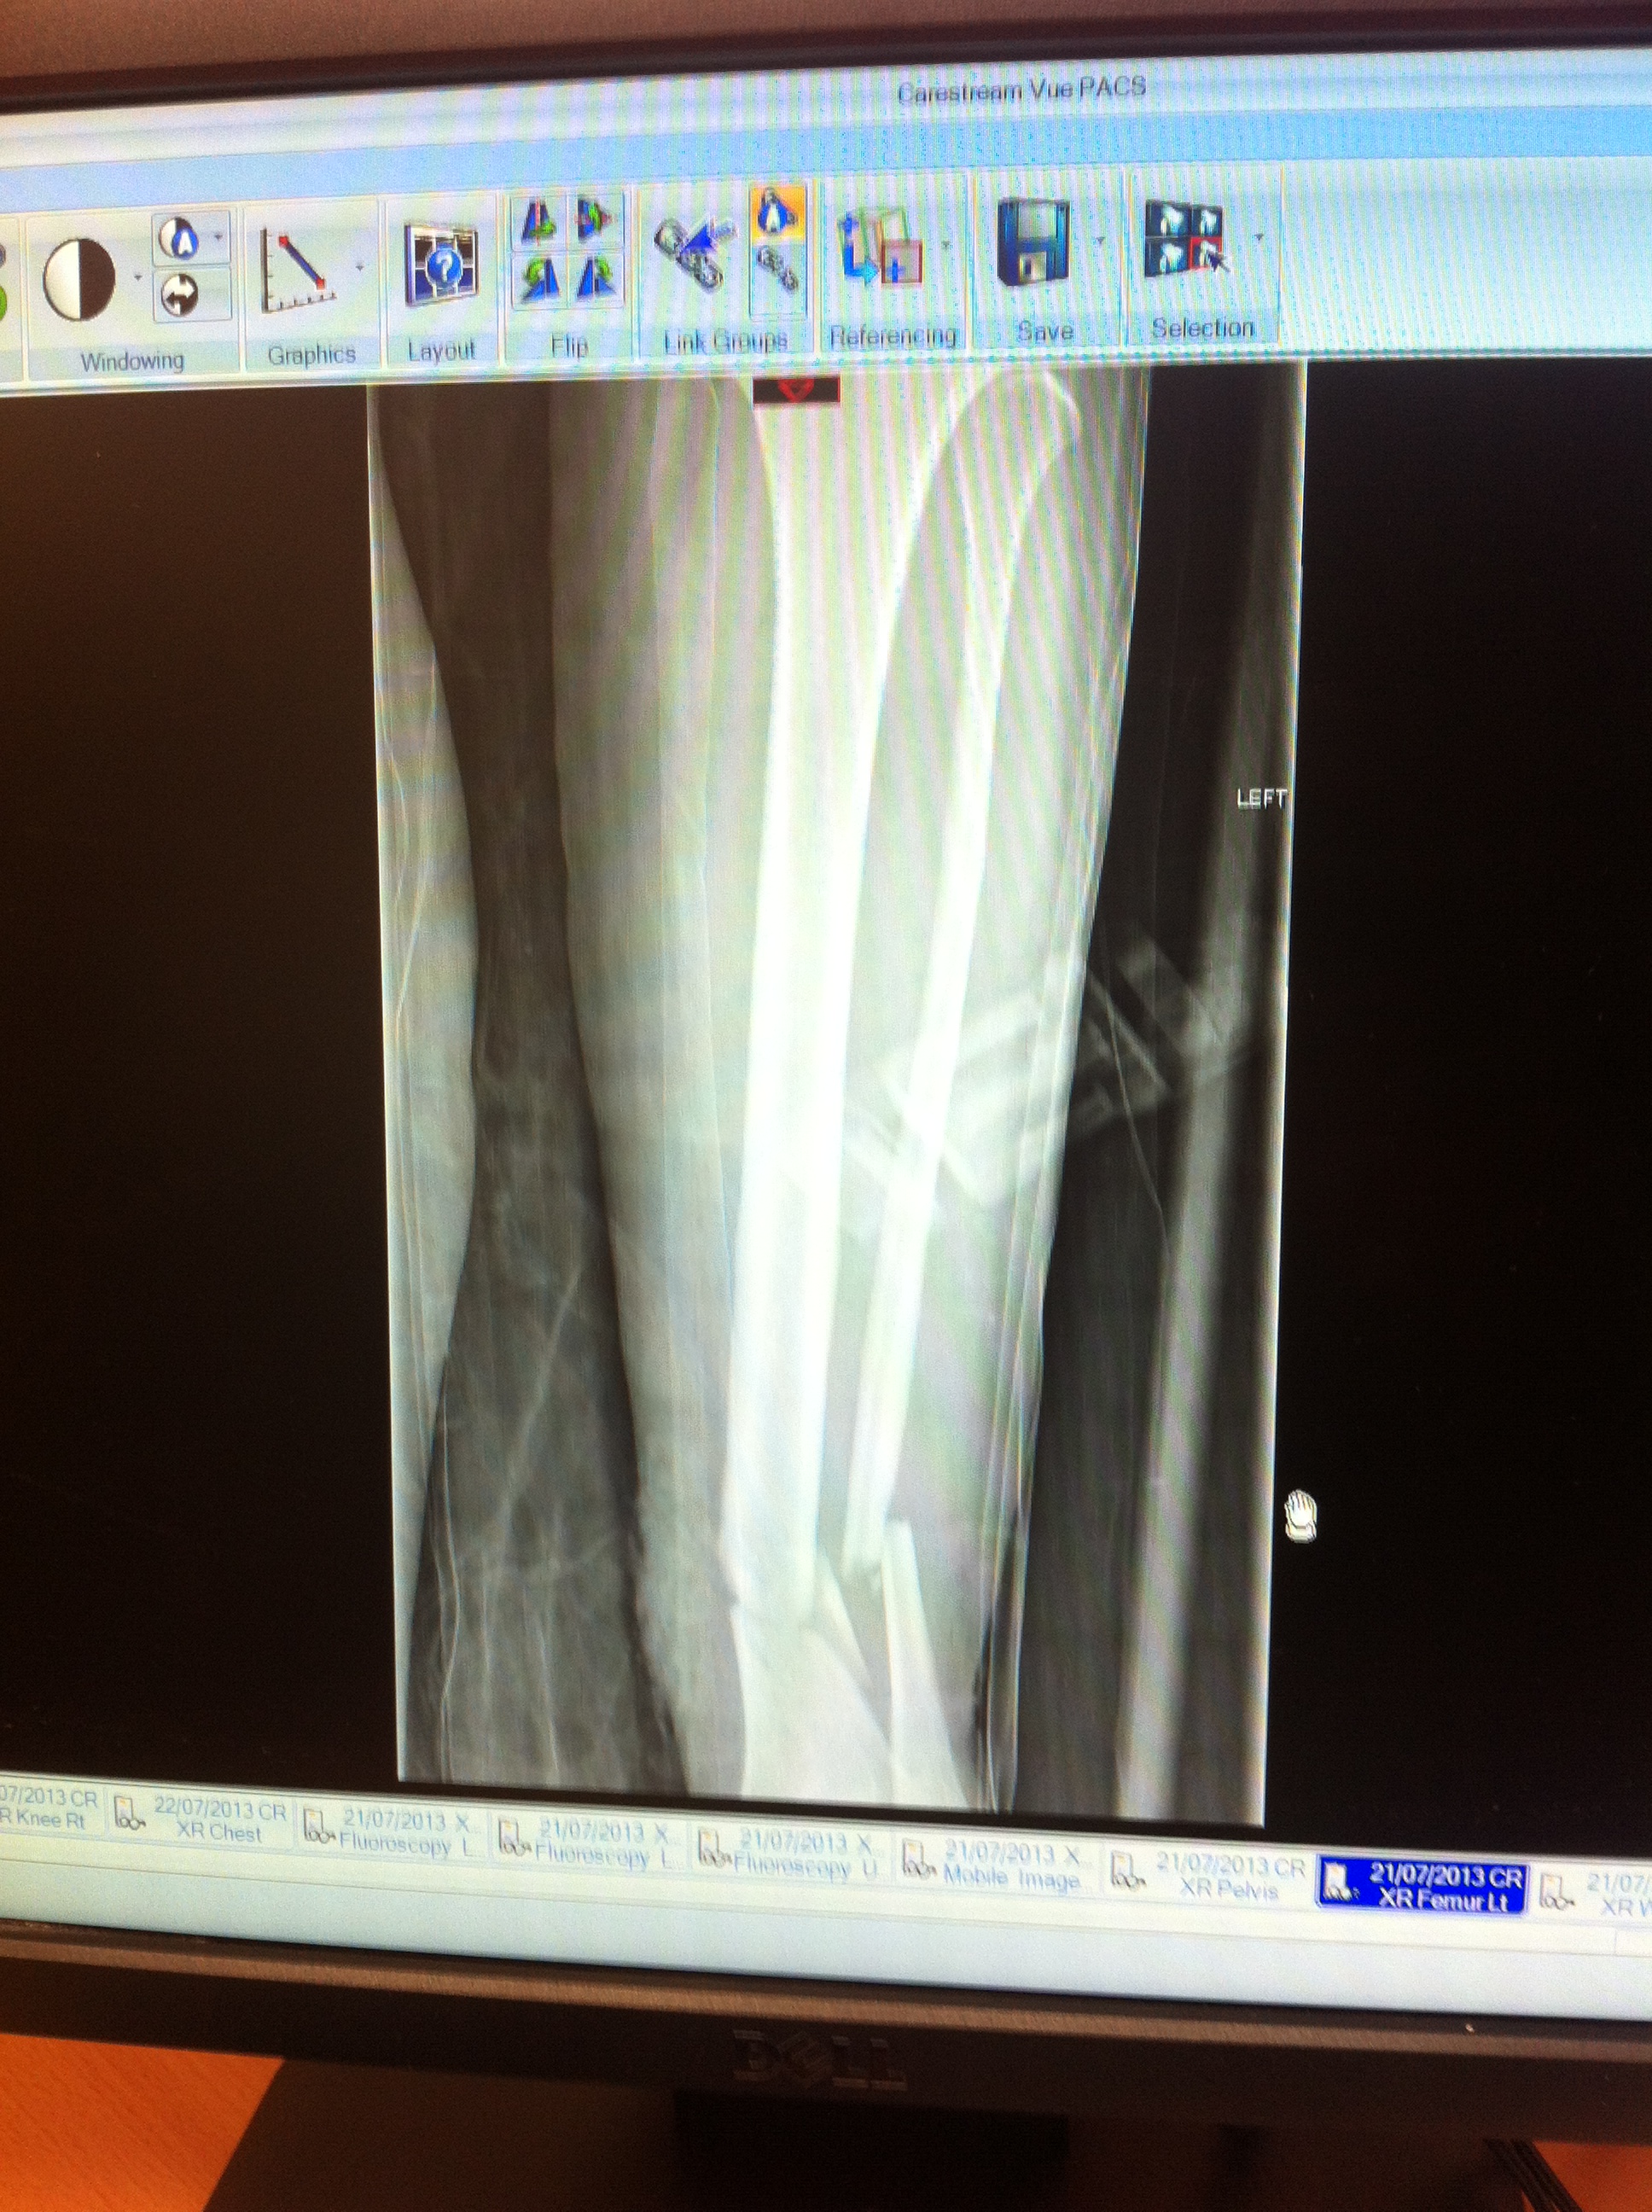

Tib/Fib

Pretty impressive collection of fractures – never bothered seeing the rib ones. Ok, 10 of them were smashed, but I figure that I’m not going to see that much that clearly.

Finally seeing the original x -rays has made me realise how bad my fractures actually were. It still sounds bonkers when I say it, but, in my head, I wasn’t that poorly.